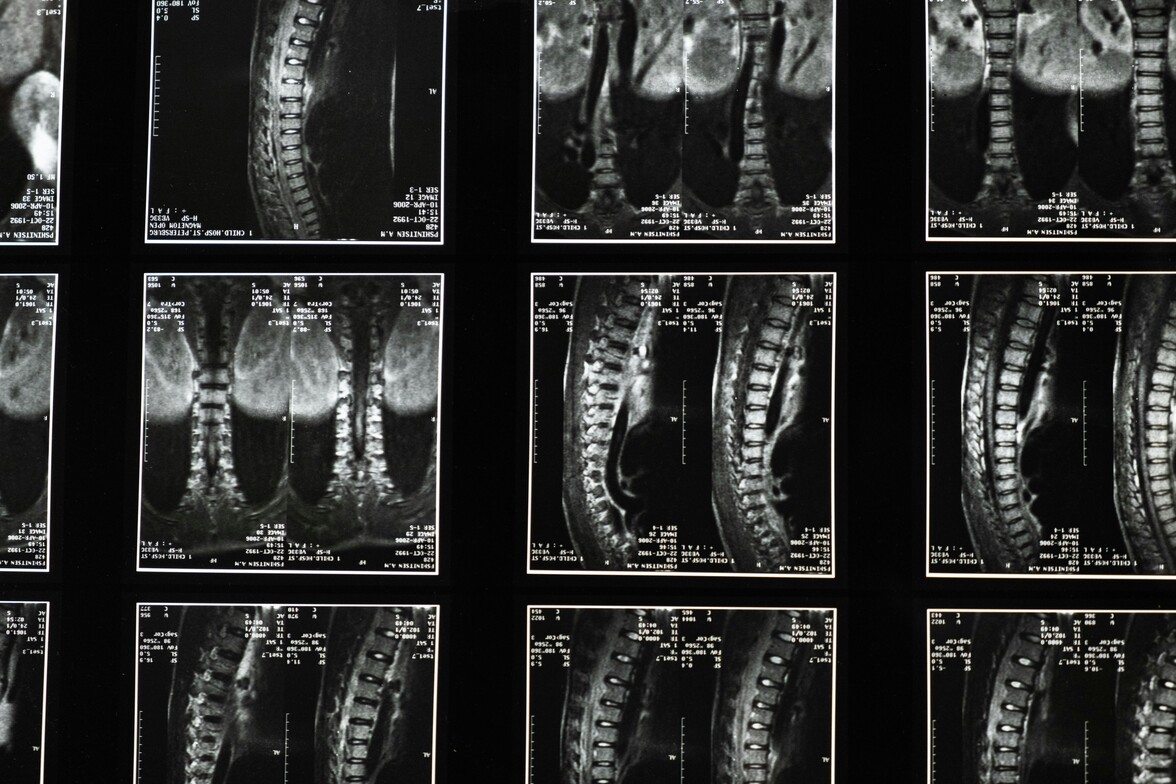

These are remarkable results. Seeing a chiropractor dramatically decreases your odds of getting back surgery, plus the chiropractic patients in this report "had lower odds of chronic work disability" and they also had fewer expensive MRI tests.